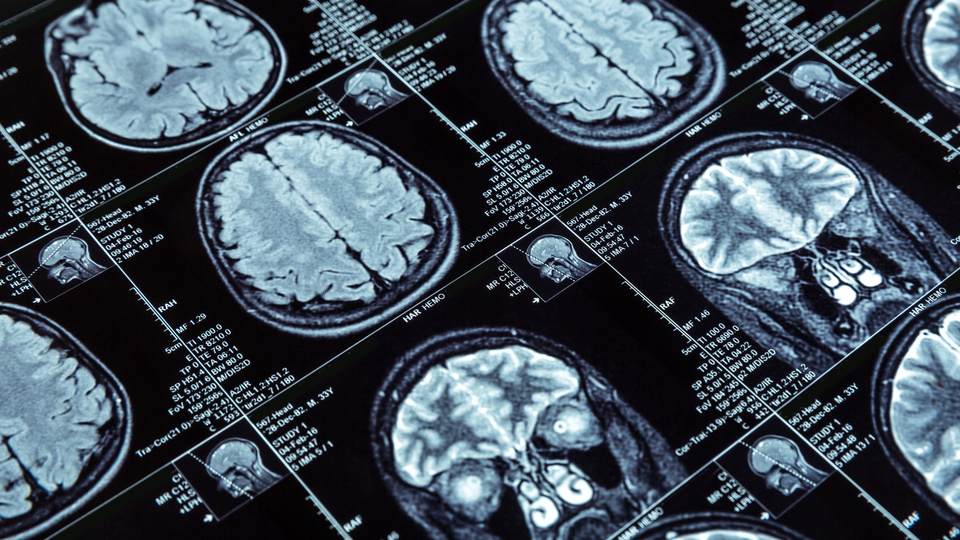

Kılıç, durumunun müdahale edilmesi gereken ciddi bir sağlık sorunu olabileceğini anladığında 3 gün geçtiğini aktararak şunları söyledi: "3 gün sonra bir nöroloji uzmanına başvurdum. Doktorum muayene ve MR incelemelerini yaptı. MR sonuçlarına göre beyin damarlarımda tıkanıklık olduğu ortaya çıktı. Hastane yatışım yapıldı ve tedavime başlandı. Taburcu edildikten sonra da denge fizyoterapisi ve medikal tedavim devam etti. Şimdi kendimi çok daha sağlıklı hissediyorum; dengemi koruyabiliyor ve daha net konuşabiliyorum. Günlük işlerimi yapıyor, ailem ve dostlarımla vakit geçirebiliyorum."

Uzm. Dr. Mustafayev, “Beynin bir kısmına giden kan akışı azaldığında veya kesintiye uğradığında, beyin dokusunun oksijen ve besin almasını önleyen bir inme (felç) meydana gelir ve beyin hücreleri dakikalar içerisinde ölmeye başlar. İnmenin oluştuğu bölgedeki fonksiyonlarda geçici ya da kalıcı kayıplar oluşur. Bu nedenle erken müdahale oldukça önemlidir. Özellikle konuşmada bozulma, dengesizlik, vücudun bir tarafında uyuşma veya güçsüzlük, çift görme gibi belirtiler hissedildiği an, ilk 4 saat içerisinde ‘İNME’ şüphesi ile 112 Acil Çağrı Merkezi’nin aranması gerekmektedir. Hastamız Begüm Kılıç, belirtileri başladıktan 3 gün sonra tarafımıza başvurdu. Daha vahim bir tabloya dönüşmeden hastaya gerekli müdahaleleri yaptık ve tedavisine başladık. Böylece olası beyin hasarını ve diğer komplikasyonları azaltmak mümkün olabildi. Etkin tedaviler sayesinde felçten kaynaklı sakatlığın önlenmesi sağlanmış oldu” diye konuştu.